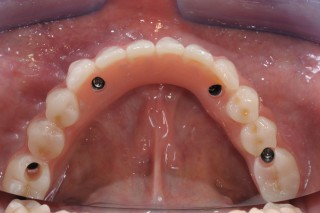

Die Kaufunktion wird innerhalb 24 Stunden ab Eingriff wiederhergestellt; die Prothesen (Zahn, Brücke, vollständiger Zahnbogen) werden gleich nach Zahnextraktion ans Implantat geschraubt.

Jüngste wissenschaftliche Studien belegen, dass die sofortige Belastung eines Implantats den Heilungsprozess des Zahnfleisches und des Knochengewebes besser ankurbelt, wodurch die Wartezeit der traditionalen Implantologie wesentlich gekürzt und die Kaufunktion des Patienten viel schneller wiederhergestellt wird.

Das Implantat kann nun positioniert werden; dabei ist zu berücksichtigen, dass die Primarstabilität (d.h. die mechanische Stabilität des Implantats nachdem es am Knochen befestigt wurde) für eine optimale Osseointegration von grundlegender Bedeutung ist. Die Weichgewebe rund um das Implantat werden vernäht und es wird ein Abdruck für die Prothese angefertigt, welche gleich eingefügt werden kann und somit die Kaufunktion des Patienten wieder ermöglicht.

Sollten Brücken und vollständige Zahnbögen vorhanden sein, ist es ratsam sich vorerst einer CT (Computertomographie) zu unterziehen um die Knochendicke und -breite dreidimensional überprüfen zu können. Nachdem die ideellen Stellen zur Einfügung der Implantate lokalisiert werden, wird eine chirurgische Schablone hergestellt, die eine schnelle und genaue Positionierung des Implantats ermöglicht (sogenannte schablonengeführte oder computerassistierte Chirurgie).